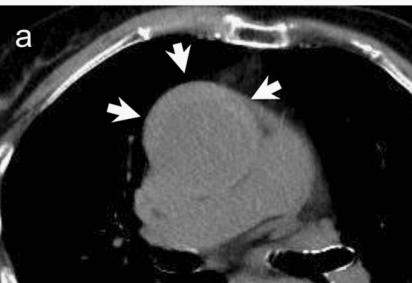

CT这么模糊,平扫怎么看主动脉夹层?

不着急!仔细看,血管里面的“血液”居然钙化了!这叫血管钙化内移,要警惕主动脉夹层!有研究发现,血管钙化内移诊断动脉夹层的特异性高达90%。

用箭头标记了,并且是增强CT,这是主动脉夹层!